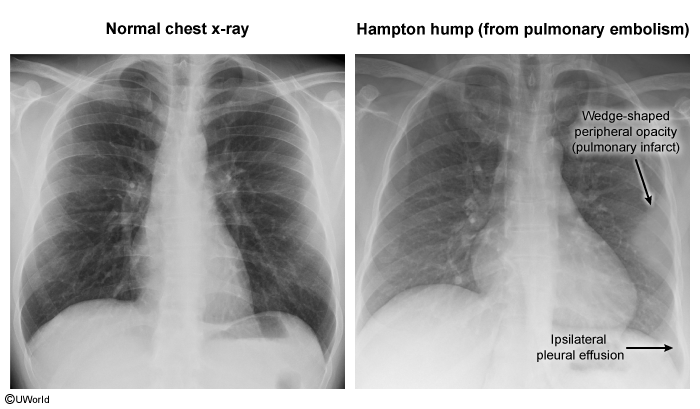

- Clinically, it presents with pleuritic chest pain and hemoptysis. Radiologically, it may appear as a wedge-shaped infiltrate (Hampton’s Hump).

- CXR: Usually normal. Rare signs: Hampton Hump (wedge opacity), Westermark Sign (oligemia).